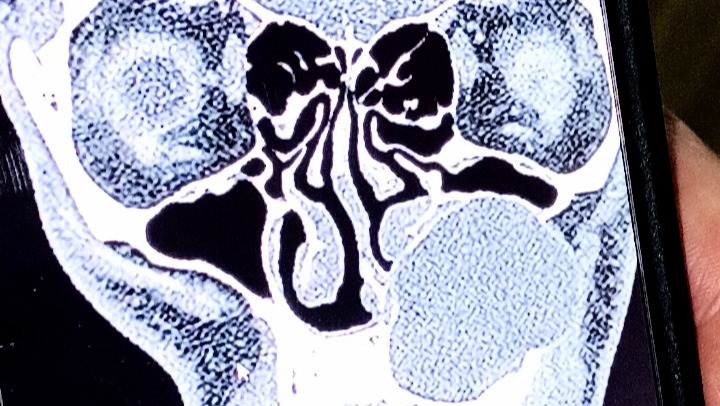

Hello, my name is Jason Palmer. I Am Only 29 & honestly I havent really spent much time thinking about my future lately because I have spent the last few weeks going to every hospital in a 200-mile radius because of a cyst under my left eye causing rampant decay to my bone. It's trying to make me go blind. I'm losing my eyesight and it could kill me if it's left untreated There are only two surgeons who can remove one of this size, Both Are 3 Hours Away If I don't have this surgery, my family will lose me, the first surgery is the most important it could save my life I don't want my 2-year-old to grow up without his dad with me having these medical problems I've had to quit my job and we only have one income and that's my wife's we have gotten really far behind on our bills we're gonna probably lose our house and our car and my wife is doing everything she can to keep everything together but it's definitely a two-person job one that I haven't been able to help with recently so if you can help at all you would releive some pressure on my wife as we go through these difficult surgeries